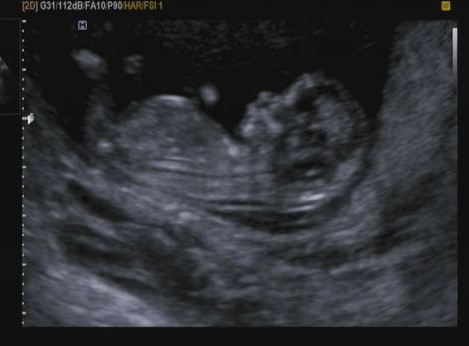

[12w1d] 2016년 4월 27일 1차 정밀초음파, 1차 기형아 검사

이번에는 12주차라 1차 기형아 검사를 앞두고 병원가는날! 그리고 1차 정밀초음파! 미리 예약했던 정...